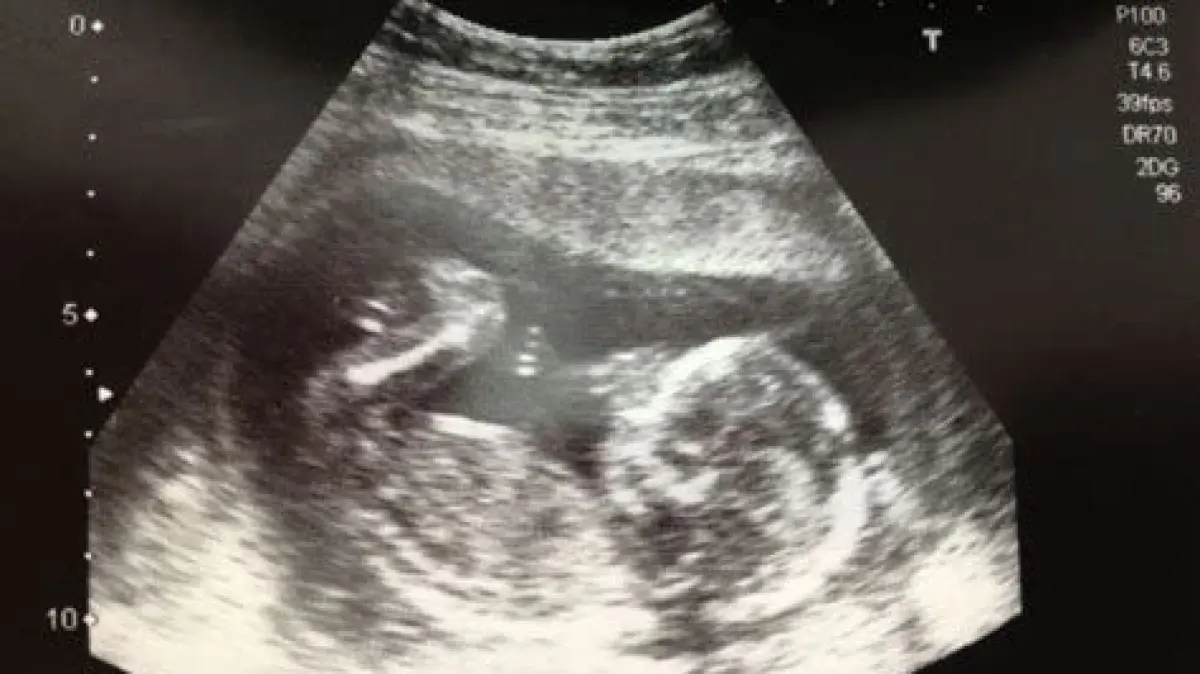

- USG: USG dapat memberikan gambaran visual tentang kondisi janin, termasuk detak jantung dan pertumbuhan organ.